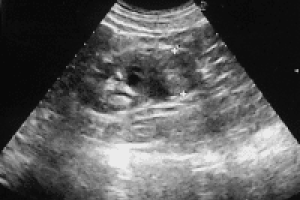

1. Kvinder

Kræft i livmoderen, Fibromer i livmoderen, Slimhindefortykkelse i livmoderen (hormonforstyrrelser),

Kræft i æggestokken (ovariecancer), Godartet forstørrelse af æggestokken, Cyste i æggestokkene, Forstørret æggeleder, Ansamling omkring æggestokken m.m.

Normal livmoder

Normal livmoder m. spiral

Æggestok Cyste

Æggestok kræft